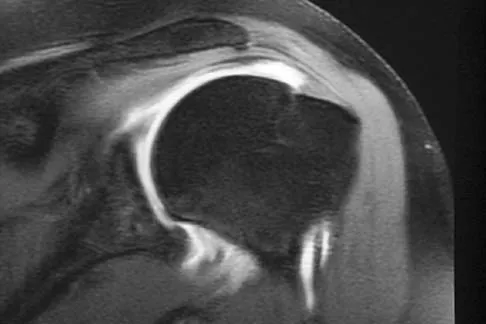

A 60-year-old woman with a history of breast cancer has progressive paraparesis. The MRI scan is shown in Figure 28. What form of management is most likely to restore or maintain ambulation?

Explanation